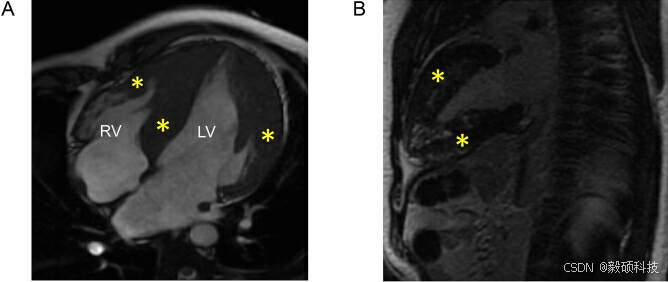

为了对 PRKAG2 心肌病患者进行深度表型,研究组对三个家族的 8 名受试者进行心脏磁共振成像(CMR)检查。研究显示,重症患者存在弥漫性严重同心左心室肥厚和右心室肥大。为了了解 3 个家族中观察到的肥厚型心肌病表型的因果变异,对43 人进行全外显子组测序。并进行联合变异调用,结果发现了 102 051 个核苷酸变异。

图5 患者 CIII-5 的心脏核磁共振成像(SSFP Cine 序列)显示,心尖四腔切面中,室间隔和左心室侧壁区域明显肥厚(黄色星号),右心室游离壁肥厚(红色星号)(A)。两腔长轴切面显示前壁和下壁左心室中壁晚期钆增强斑片状区域(黄色星号)(B)。